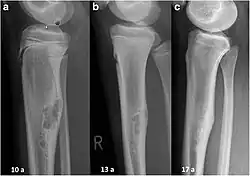

| Non-ossifying fibroma of tibia | |

The most common bone tumor is a non-ossifying fibroma.[4] Average five-year survival in the United States after being diagnosed with bone and joint cancer is 67%.[5] The earliest known bone tumor was an osteosarcoma in a foot bone discovered in South Africa, between 1.6 and 1.8 million years ago.[6]